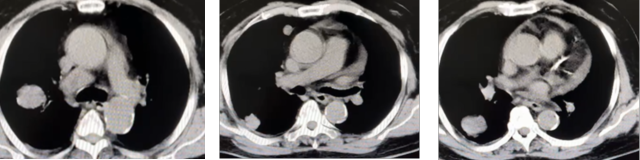

2024 年 10 月复查胸腹 CT

右肾切除术后态,局部低密度与肝脏及右肾上腺分界不清,请结合临床

双肺多发结节及肿块,纵隔肿大淋巴结,考虑转移支气管炎

心脏增大,心包积液,冠状动脉钙化左肾囊肿可能,请结合超声左肾周桥隔增厚

2024.7.13 开始服用伏罗尼布,10.13 复查 CT,双肺多发结节,大者位于右肺下叶,长径约 3.8cm,纵隔内见肿大淋巴结,长径约 3.7cm。

2025.2.27 复查 CT,右肺下叶结节 2.1cm,纵隔淋巴结 3.7cm。